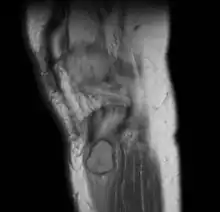

A well-defined area of bone loss in the medulla of the bone is seen on x-ray.[2]

MRI right knee: periosteal chondroma